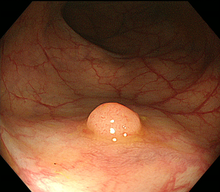

図 大腸ポリープ

1)内視鏡的ポリープ切除術(ポリペクトミー)

大腸に隆起したポリープを認めた場合、ポリープの茎の部分に、内視鏡を通して通電ワイヤー(スネア)を掛け、ポリープを締め上げて高周波電流で切除します。高周波で切除することにより、切除した部位に熱凝固という作用が起きて止血できます。大腸粘膜には知覚神経がないため切除時には痛みは感じません。ポリープの大きさや形状によって1日から数日間の入院が必要です。